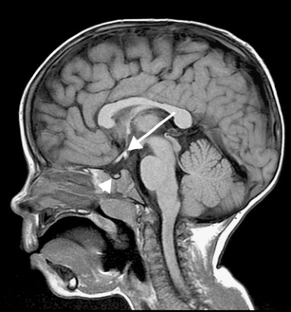

Patients with congenital hypopituitarism might have the classic triad of pituitary stalk interruption syndrome, which consists of: (1) an interrupted or thin pituitary stalk, (2) an absent or ectopic posterior pituitary (EPP), and (3) anterior pituitary hypoplasia or aplasia.

Fig. 3